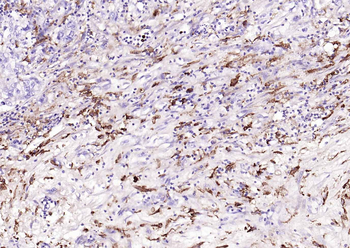

100 μl, 200 μl, 50 μl - Featured

FC, ICC, IF, IHC-Fr, IHC-P, WB

Human, Mouse, Rat

Bovine, Canine, Equine, Gallus, Porcine

Rabbit

Polyclonal

Unconjugated

100 μl, 200 μl, 50 μl - RORC Rabbit Polyclonal Antibody [orb6888]Featured